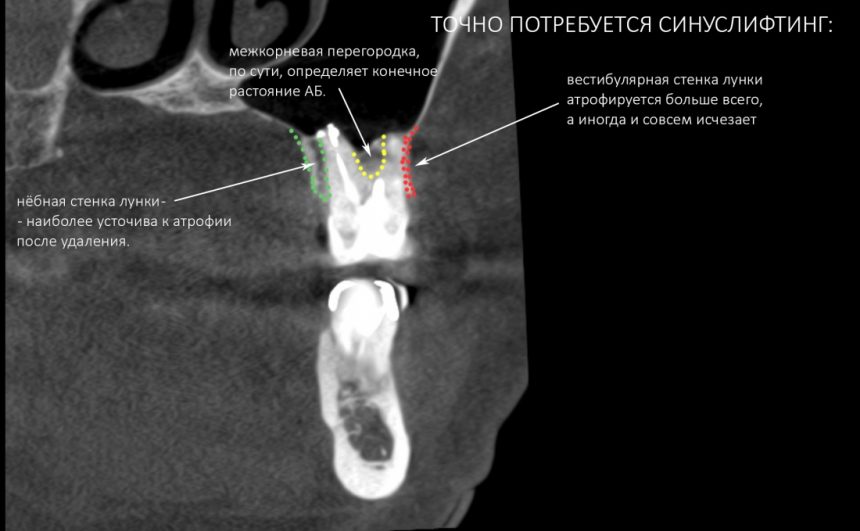

Анатомия: Межкорневая костная перегородка